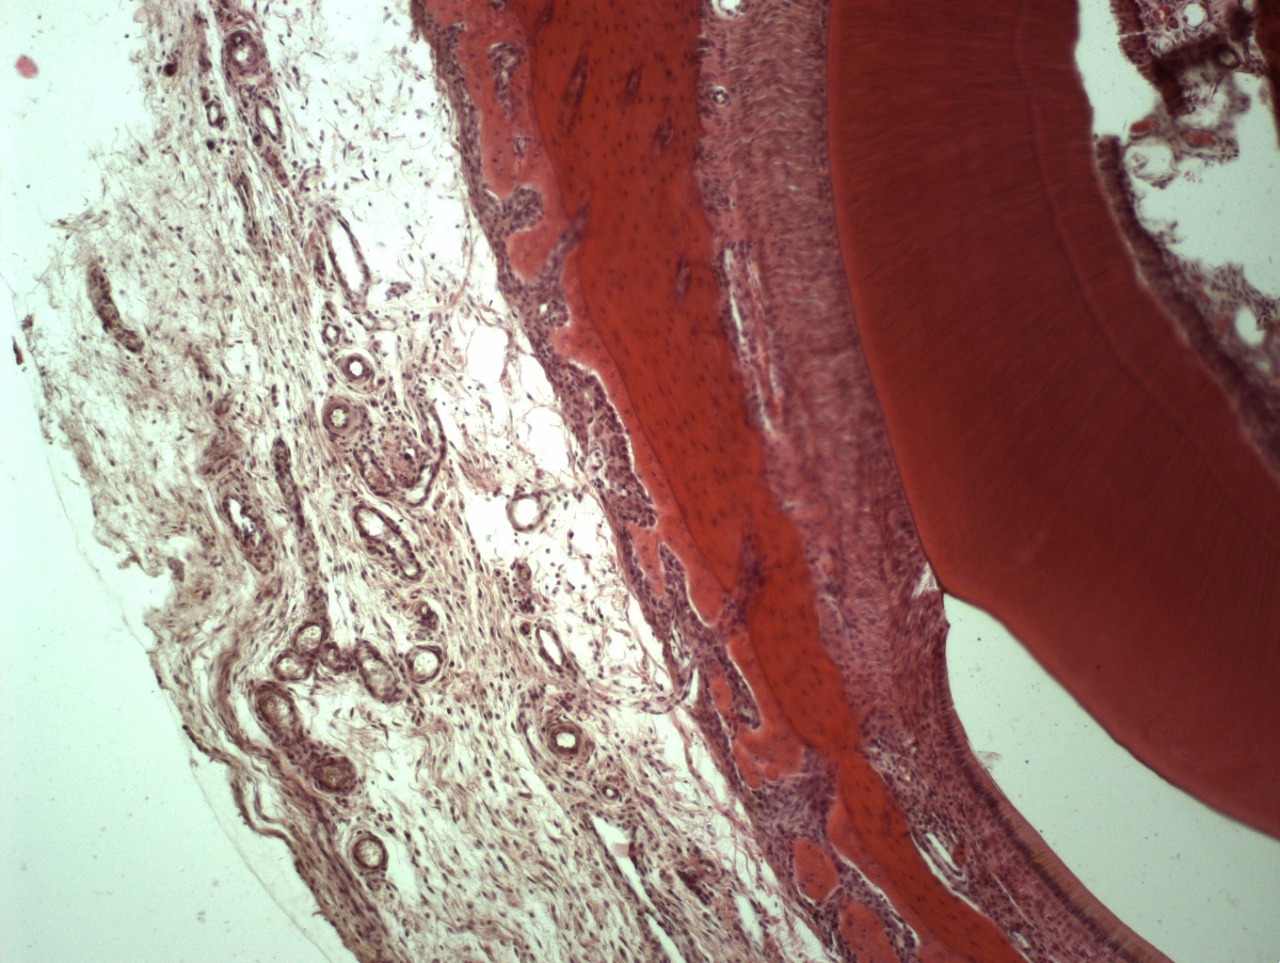

• Например, таким образом удаляются все следы жира, белка, нуклеиновых кислот, мертвых клеток и их компонентов, неколлагеновых белков и прочих соединений. Вследствие такой очистки остается только коллагено-минеральный каркас мертвого межклеточного вещества костной ткани, состав которого стабилен на протяжении всей жизни человека.

• При последующей лиофилизации вся свободная и связанная влага испаряется из кости, и она [кость] немного сокращается в объеме, как бы «подседает», на 10-15%.

• При этом во всем объеме пористой структуры возникает так называемый «капиллярный эффект», или отрицательное поверхностное натяжение, или разряжение.